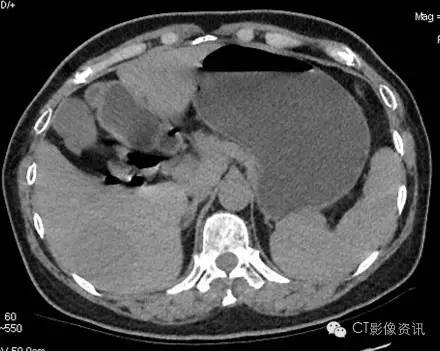

各期扫描及CT值测定 平扫

病灶内CT值:55.13

动脉期

病灶内CT值:160.26

静脉期

病灶内CT值:144.22